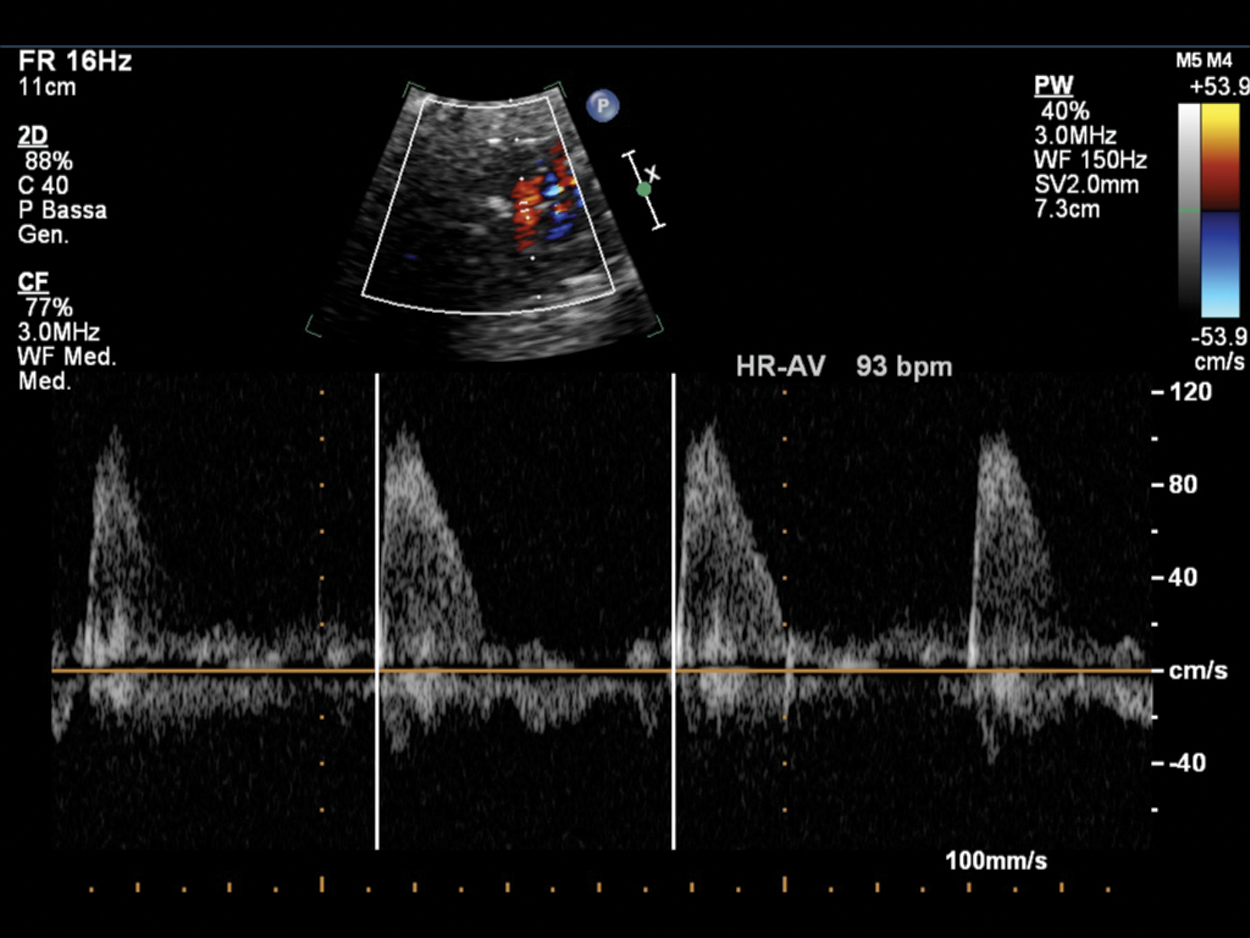

Figure 12: Fetal bradycardia (FHR 93 bpm) in a pregnant at 35 GA probably due to LQTS; the suspicion is related to the family history of a previous son who died at 2 months of life for LQTS and noncompaction myocardium. PW Doppler cursor placed through aortic valve. HR-AV: Heart rate—aortic valve

Pulsed Doppler (Figs. 4–12) recordings of simultaneous left ventricular inflow and outflow, superior vena cava and ascending aortic flow, or pulmonary artery and pulmonary venous flow permit documentation of the relationship between mechanical atrial and ventricular systole [6].